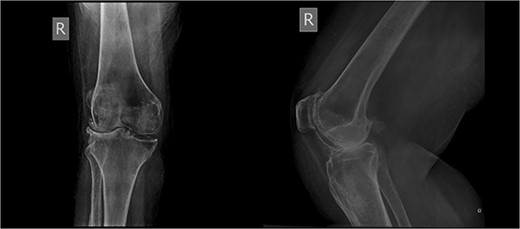

An 86-year-old female patient with a body mass index (BMI) of 31.2 presented to our outpatient department with severe right knee pain. Physical examination revealed a mechanical block of the knee, limiting its range of motion (ROM) between 10° and 55° of flexion. Plain knee radiographs showed grade 4 knee osteoarthritis (OA) in the Kellgren–Lawrence scale (Fig. 1).